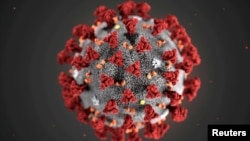

Այսօր լրանում է մեկ տարին, ինչ Առողջապահության համաշխարհային կազմակերպությունը (ԱՀԿ) Covid-19 կորոնավիրուսային վարակի տարածումը դասակարգեց որպես «համավարակ»՝ համաշխարհային համաճարակ։

2020 թվականի մարտի 11-ին ԱՀԿ-ն ամբողջ աշխարհում վարակի118 հազար դեպքի պայմաններում Covid-19-ը հայտարարեց համավարակ՝ ընդգծելով, որ սա ոչ միայն հանրային առողջապահական ճգնաժամ է, այլև ճգնաժամ, որն ազդելու է բոլոր ոլորտների վրա։

Նոր տեսակի կորոնավիրուսը որպես համավարակ դասակարգելուց մեկ տարի անց աշխարհում վարակման հաստատված դեպքերի ընդհանուր թիվը գերազանցել է 117 միլիոնը։ Covid-19-ից մահացել է ավելի քան 2 միլիոն 600 հազար մարդ։

Առաջին անգամ Չինաստանի Վուհան քաղաքում հայտնաբերված կորոնավիրուսի համավարակն այժմ դարի մեծագույն առողջապահական մարտահրավերներից մեկն է։ Covid-19-ի բնօրրան համարվող Չինաստանում այժմ համաճարակային իրավիճակը համեմատաբար կայուն է։ Մինչդեռ աշխարհի մյուս երկրներում վարակը շարունակում է մոլեգնել։ Մեկ տարի անց աշխարհի մի շարք երկրներ կրկին փորձում են ավելի խստացնել կարանտինային սահմանափակումները՝ կանխելու կորոնավիրուսի տարածման աճը։